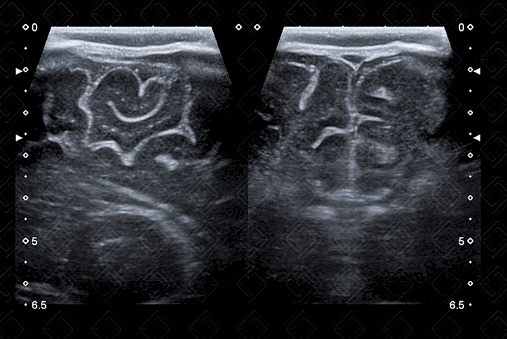

As imagens rotineiramente são obtidas nos planos coronal e sagital. As imagens coronais são obtidas colocando-se o transdutor transversamente pela fontanela anterior e angulando o feixe de ultrassom da frente para trás. As imagens sagitais são obtidas posicionando-se o transdutor em orientação longitudinal na fontanela anterior e angulando o feixe do meio para lateral (figuras 1 a 6).

Descrição das figuras 4 e 5: Ultrassonografia transfontanela, planos parassagitais direito e esquerdo, varrendo até o nível da ínsula.